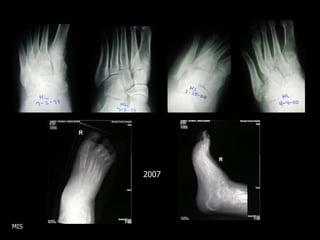

MIS

2007

Diabetic Charcot Arthropathy

Case Presentation